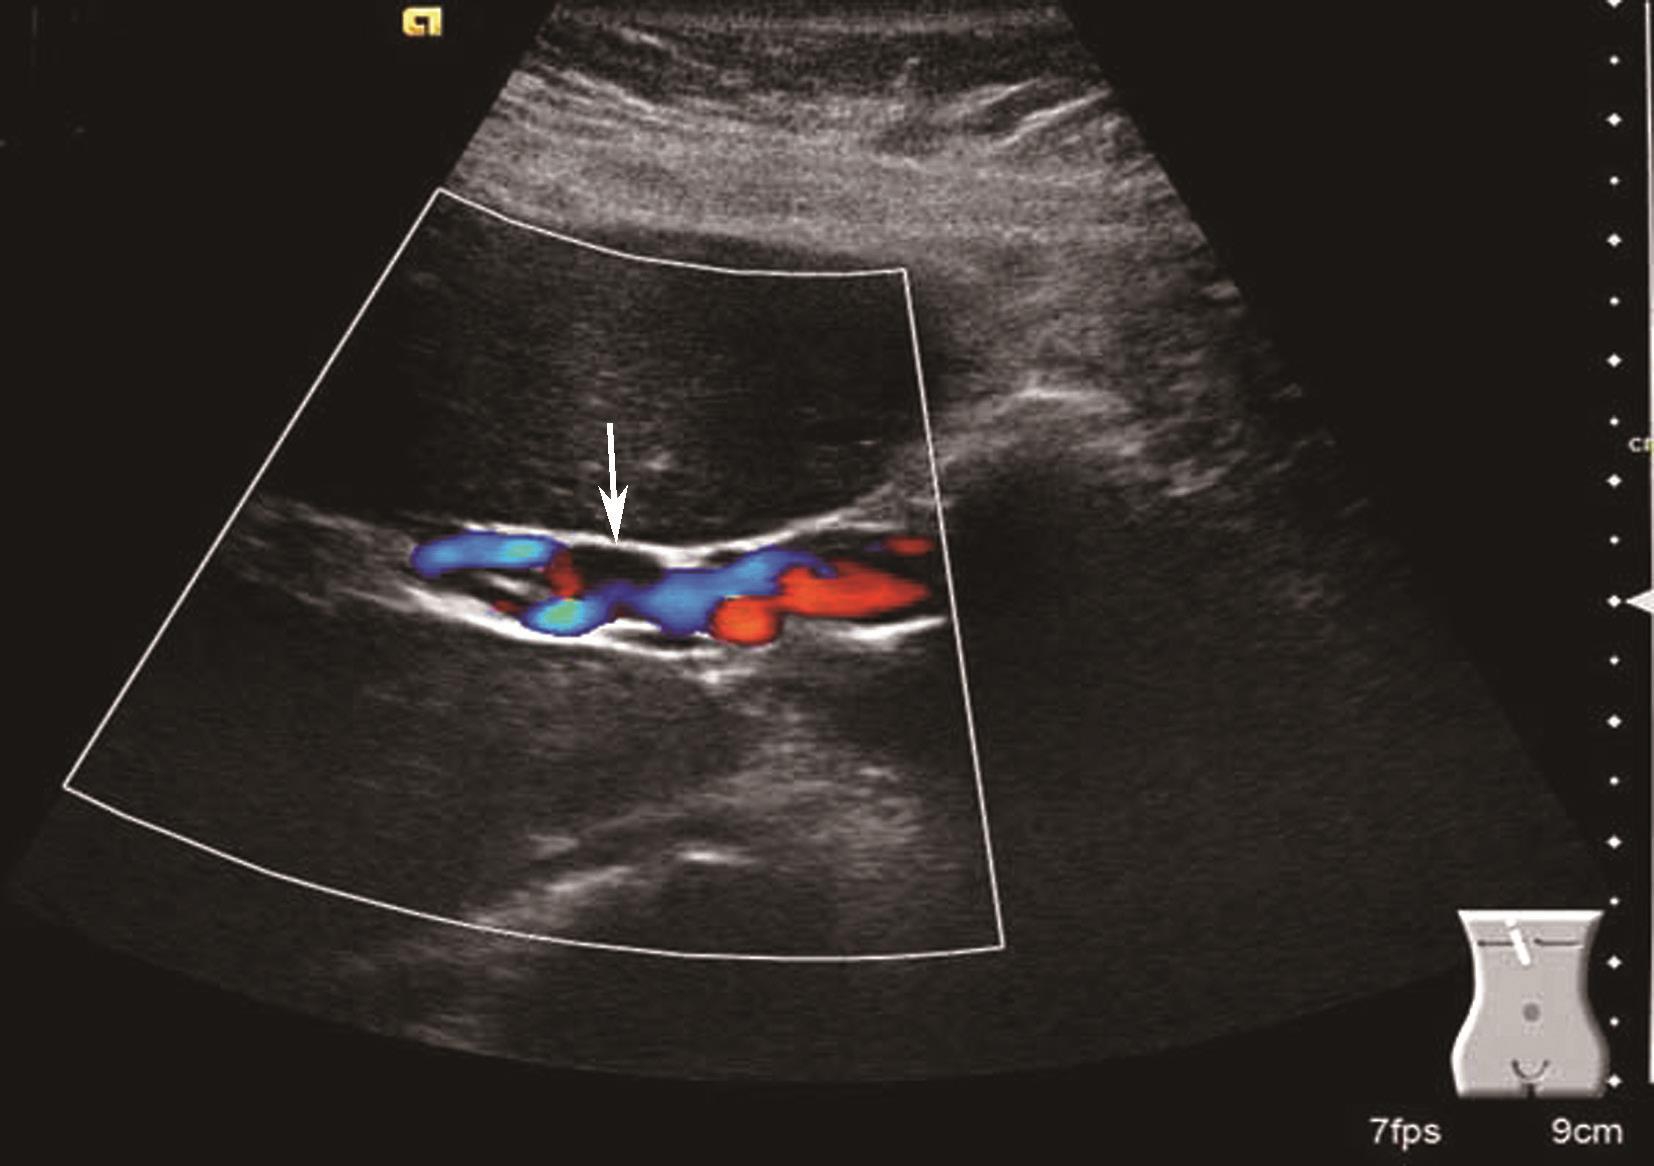

(3)肝血管:

肝内血管网变少。①门静脉高压:门静脉系统血管粗细与门静脉压力呈正相关。门静脉主干内径≥1.4cm,彩色多普勒显示门静脉色彩暗淡,严重者门静脉内显示双向血流或离肝血流,频谱多普勒超声检测正常的轻度波动消失,血流频谱低平或双向、反向血流,峰值流速一般低于20cm/s,同时脾静脉(内径≥0.8cm)及肠系膜上静脉增宽(内径≥0.7cm),有时可见呈瘤样扩张或脾肾静脉分流,部分患者可见门脉血栓形成及海绵样变性。②肝静脉可受挤压变细或粗细不均,血流频谱。部分肝静脉变细,纹理紊乱,仅见粗细不均、迂曲的蓝色血流。多普勒频谱曲线S<D峰,或S、D峰相连呈驼峰。③肝内动脉:肝硬化后,由于门静脉循环障碍,可使肝动脉代偿性扩张和增生,并与门静脉吻合支沟通。结果使肝动脉血流量增加,二维灰阶显示肝动脉内径增宽,彩色多普勒超声显示肝门部与门静脉并行的搏动性血流信号,脉冲多普勒超声可测得较高的峰值血流速度。④侧支循环开放:脐静脉重新开放使圆韧带内已闭塞的脐静脉分离而出现管状无回声区,自门静脉左支囊部延向腹壁。彩色多普勒检查门静脉左支彩色条状管道沿圆韧带方向一直通向肝表面,并穿过肝包膜及肌层至腹壁。重新开放的脐静脉血流多少与门静脉高压的严重性呈正相关。⑤胃左静脉扩张:内径≥0.5cm,血流速度增快,血流方向向肝、离肝或双向。门静脉高压患者伴有胃左静脉扩张提示存在食管胃底静脉曲张。⑥脾大:多为中度或重度肿大。脾静脉在脾门部和脾实质内有扩张的征象,脾实质回声无明显变化或轻度增强。腹水:肝前、脾周围、肝肾间隙、腹侧、盆腔出现液性无回声区,形态不定,且随体位改变而有相应变化,最大径可超过10cm。肝硬化肝血管超声声像图表现如图5-21-5~图5-21-7所示。

图5-21-5 肝硬化门静脉扩张、腹水、门静脉-肝静脉瘘彩色多普勒图像

图5-21-6 肝硬化脐静脉扩张彩色多普勒图像

图5-21-7 肝硬化脾肿大伴脾静脉曲张彩色多普勒图像